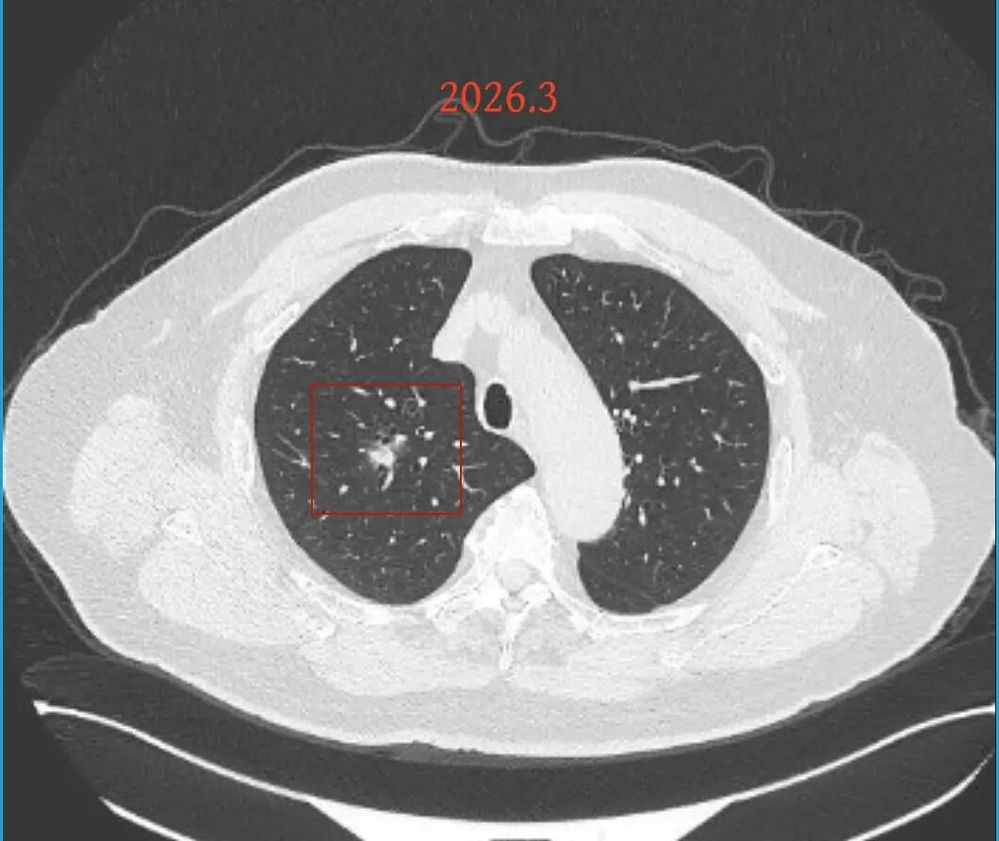

第三次问诊:2026.3

影像展示与分析:

但病灶B却显然进展!变成以实性成分为主的了!

我的意见:

两处均有进展,混合密度这处更显著些。那要考虑手术了的。之前也有碰到较短时间内进展是伴炎症或纤维增生的,但我们不能赌。建议手术为宜。意见供参考!

再看病灶B的2026年3月细节影像特征:

边缘位置也是较淡的磨玻璃成分。

上图是混合密度,轮廓较清,瘤肺边界欠清晰。

病灶A以及他处磨玻璃结节其实进展都是不明显的,略与2022年比,病灶A稍显明显点。病灶B开始时极淡,之前进展虽有但也甚微,直到2025年9月仍是磨玻璃成分为主,只是点状少许密度稍高成分。但在最近半年内却显然进展!若从影像上判断,基本上就得是浸润性腺癌了。那有几点:一是必不能再随访;二是大小来看仍是1A期;三是从快速进展来说,可能含有部分高危亚型,比如微乳头或实体型等;四是他处的磨玻璃结节以及病灶A显然不能用病灶B的转移来解释,仍考虑是多原发早期肺癌。

结友问能否先穿刺?我是这么考虑的:你这个病灶B一是位置深,且靠近附近的血管,不容易穿刺;二是从影像变化来看,基本上肯定是恶性的,不是100%,也是95%以上的概率。刚才我又在重建看冠状位与矢状位以及各次影像,目前混合密度的其实是后来者居上,原来刚开始是它比旁边的病灶密度淡的,但它的密度不是太纯,前次你自己也说似乎有点状偏实性成分。只是最近这半年进展特别快。这说明它的恶性程度较它边上原来就比较明显的那处恶性程度高,亚型中大概率有低分化的成分。所以从目前的影像来看,要尽快手术,而且切肺叶更为稳妥些。